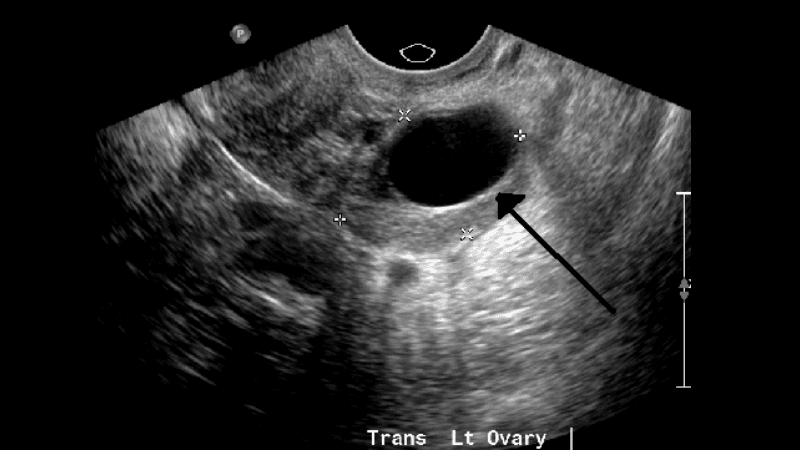

Khi thực hiện kiểm tra, hình ảnh u nang buồng trứng trên siêu âm cung cấp rất nhiều dữ liệu quan trọng giúp đánh giá tình trạng bệnh. Cụ thể, thông qua siêu âm bác sĩ sẽ nhận diện được:

- Vị trí chính xác và số lượng khối u nang.

- Kích thước, hình dạng và cấu trúc hình thái học của khối u.

- Thành phần bên trong khối u là chứa đầy chất lỏng, chất rắn, hay dạng hỗn hợp cả hai.

- Các biến chứng tiềm ẩn cực kỳ nguy hiểm như xoắn, vỡ hoặc xuất huyết từ u nang.